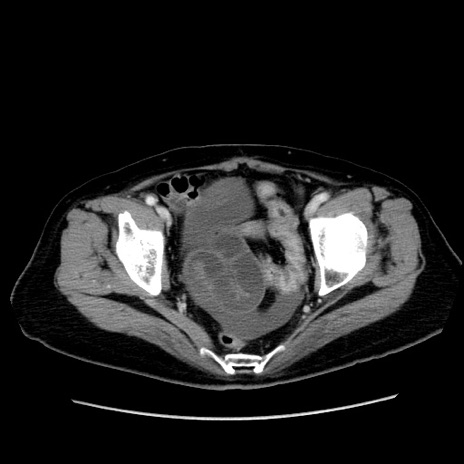

症例19(横断像)

【症例】80歳代女性

【主訴】下腹部痛

【現病歴】約8時間前より下腹部痛の出現あり、救急外来受診。

【既往歴】両側付属器切除

【身体所見】意識清明、下腹部正中に手術痕あり、その部位に一致して圧痛と反跳痛あり。腸蠕動音は亢進。

【データ】WBC 9300、CRP 0.15